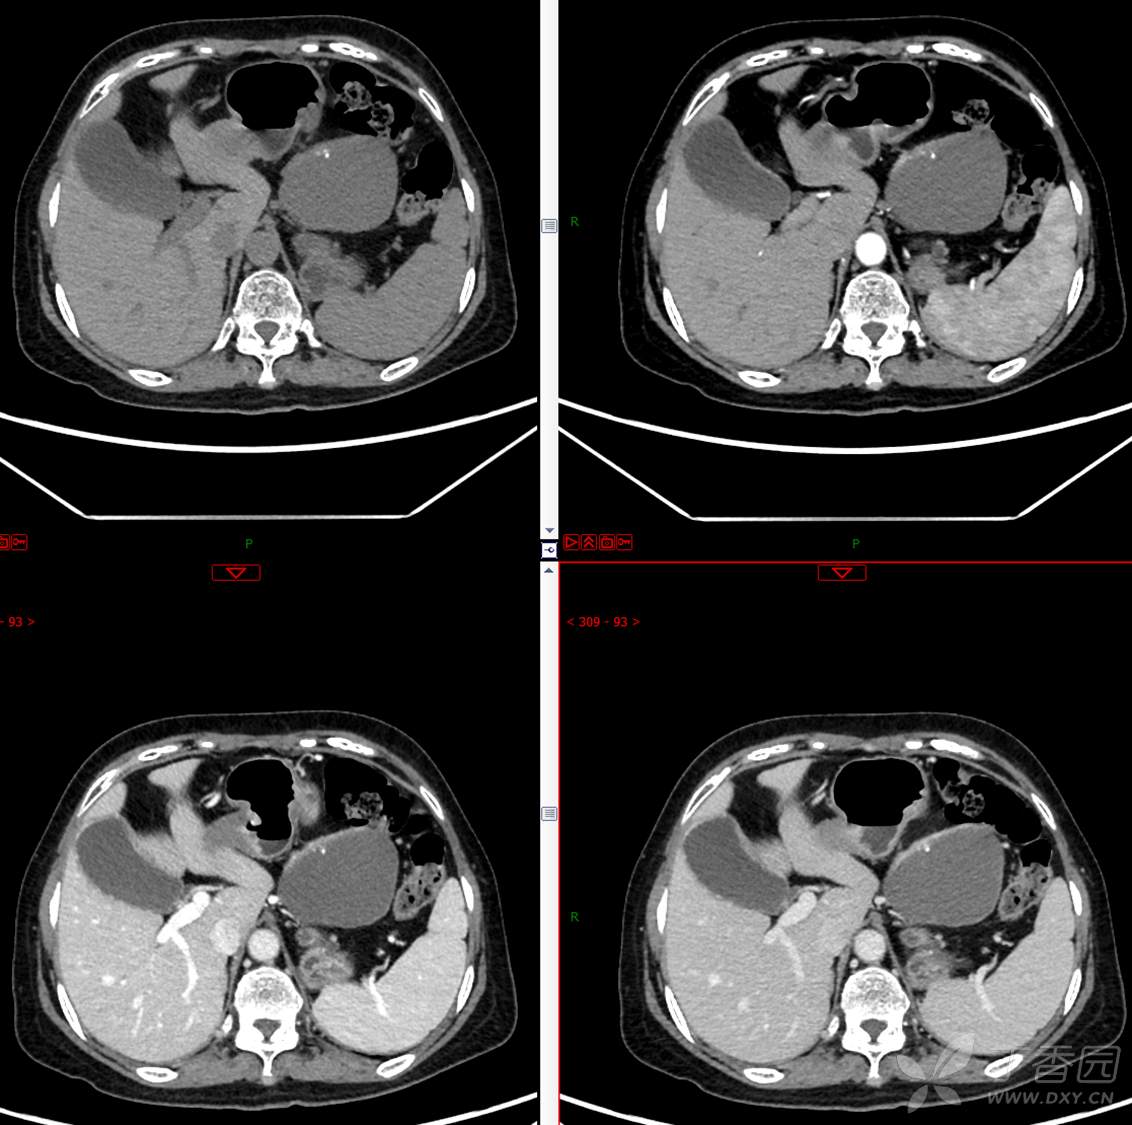

主 诉:发现胰腺占位性病变3月

现病史:患者3月前就诊于**市人民医院行腹部增强CT发现胰尾占位性病变,无腹痛、腹胀,无恶心呕吐,无黄疸,无呕血黑便,无胸闷憋气,无寒战高热,未行特殊治疗